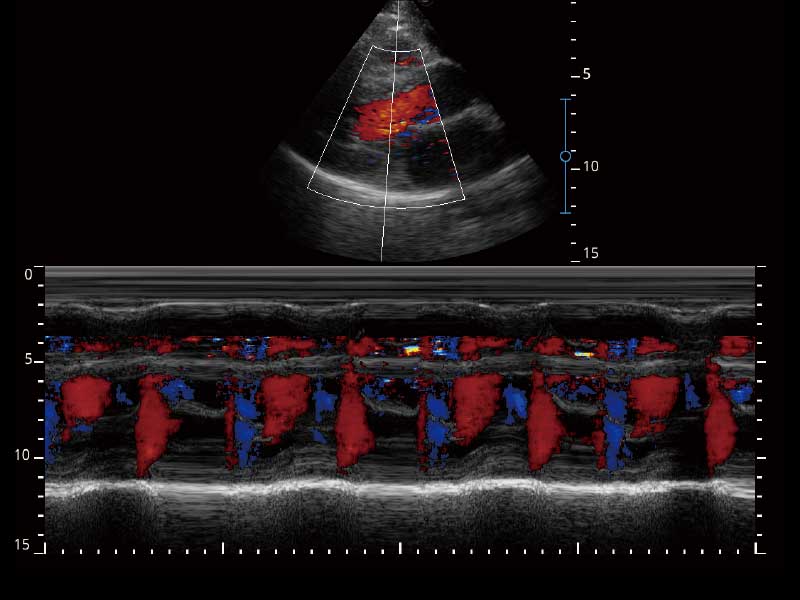

E2便携式彩色多普勒超声诊断系统采用专业的超声技术平台、高度集成化的硬件模块和结构设计、简便的操作流程、多探头接口设计,兼顾了优质图像、轻便机身以及台便两用的临床使用需求。

μ-Scan微米成像、空间复合成像、高分辨率血流成像。